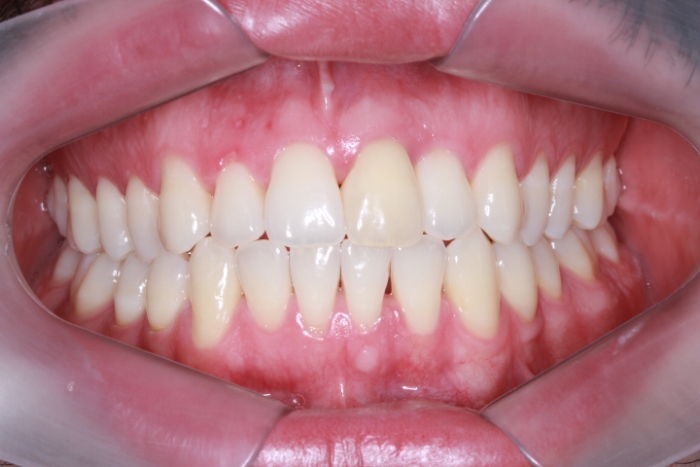

Foto Frontal Inicial 18-05-15